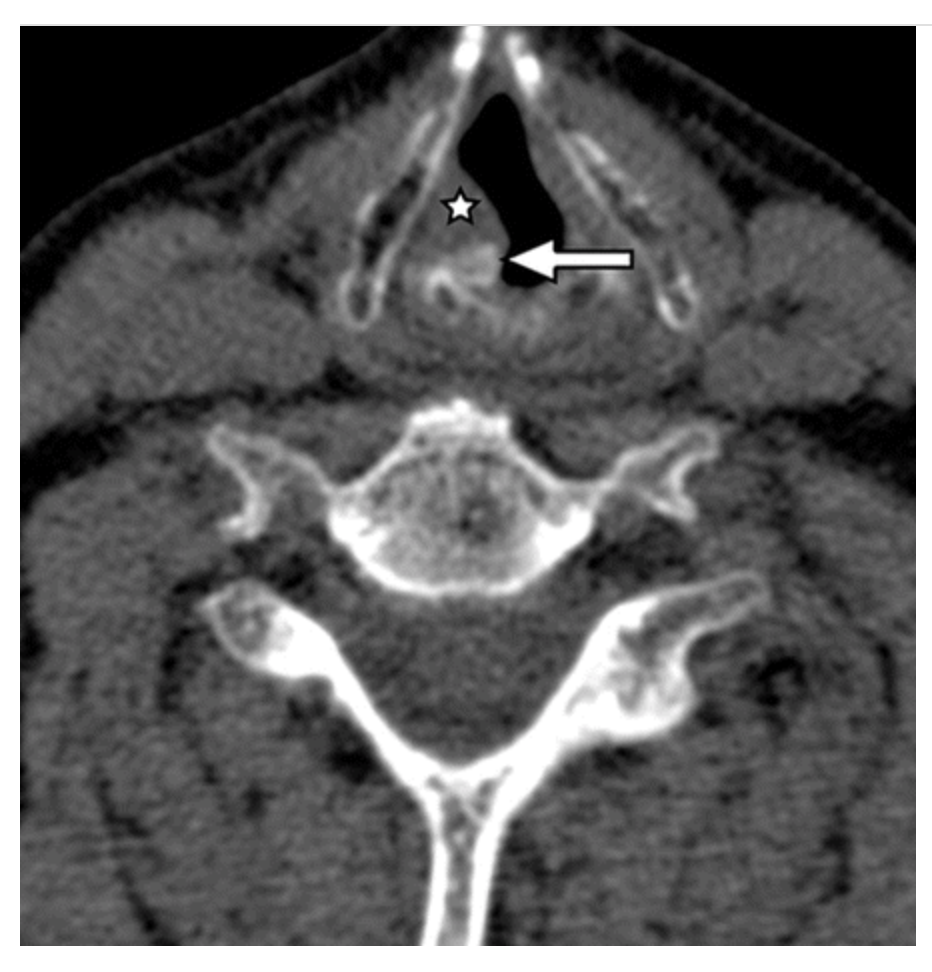

laryngotracheal separation